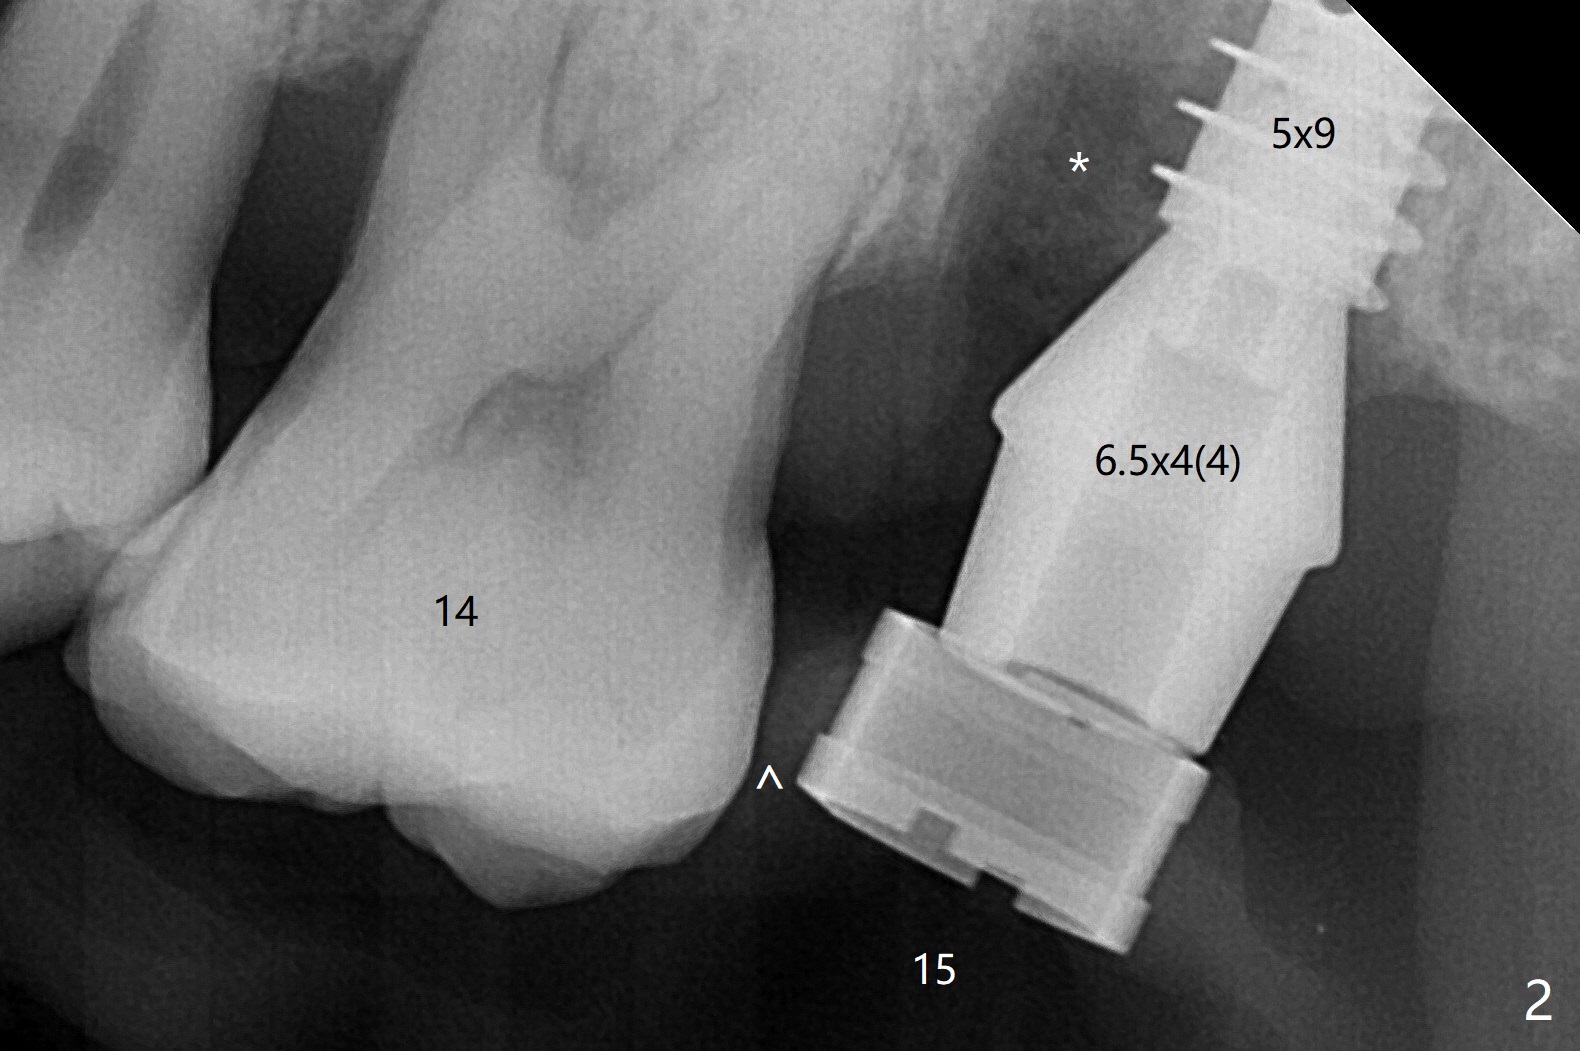

尽管腭侧(P)根周围骨质吸收严重(图三(术前设计)),15号牙拔除还挺困难,因为两个颊侧根骨质吸收不明显,而腭侧根表面许多结石(说明牙周病变)。导板使用中,金属圈脱落,插回后还能用(图一(术后拍摄)),完成种植(图二)。金属圈脱落可能是因为近中塑料太少了(图一,二:箭头)。植体(图四:绿色)和基台(粉红色)放置后,粘性骨粉植骨(红圆圈)前,在腭侧缺失处塞入一块胶原塞(浅蓝色),最后缺损充填完善(图二,五比较(*))。